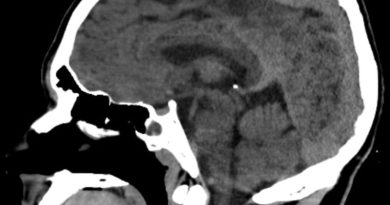

24 yaş, E

Baş ağrısı

Lhermitte duclos

Lhermitte-Duclos hastalığı (Dysplastic cerebellar gangliocytoma)

Dysplastic cerebellar gangliocytoma(Lhermitte-Duclos hastalığı)

Lhermitte-Duclos hastalığı

Displastik serebellar gangliositoma